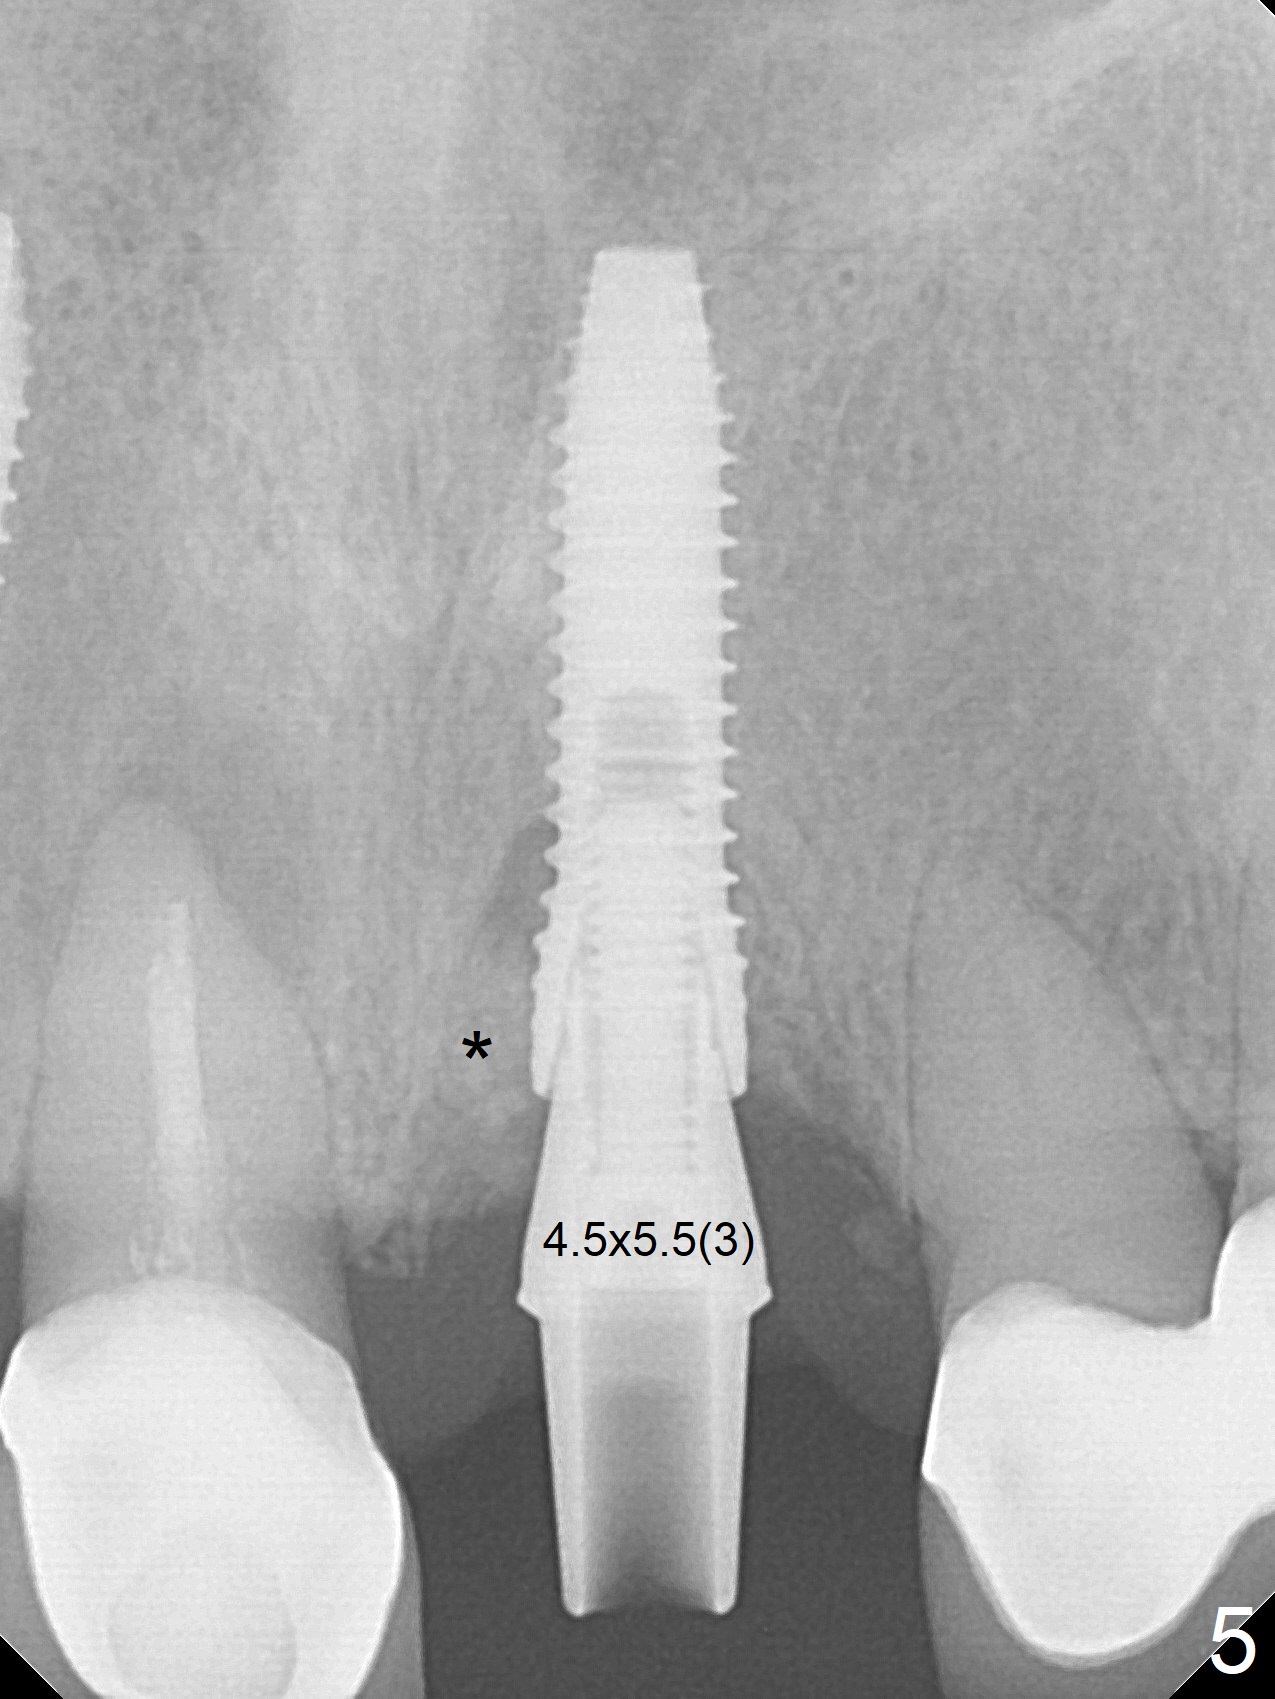

The buccal contour at #9 seems to be slightly concave preop (Fig.1,2 (*)). In fact the buccal plate is found to be lost when the tooth is extracted. Osteotomy is initiated as palatal as possible apical, but the occlusion dictates the coronal end of the osteotomy should be buccal, leaving the buccal gap ~ 2 mm for bone graft. The initial osteotomy (18 mm deep) appears to be close to the Incisive Foramen (Fig.3 blue dashed line). The nasal floor appears to be intact when the drill is removed. Subsequent osteotomy is adjusted so that the apical end of the osteotomy moves distal; when a 3.8x15 mm dummy implant is partially placed, there is clearance (Fig.4). It remains so when a definitive implant is seated (Fig.5); Vanilla graft is placed (Fig.5 *) before placement of a 4.5x5.5(3) mm abutment. More allograft is placed when an immediate provisional is fabricated (Fig.6 arrow and *). The gingiva remains to be recessive 1 month postop (Fig.7). It seems to be related to the bulky gingival margin of the provisional (Fig.8 *). After trimming the latter (Fig.9 *), the gingival margin immediately returns close to normal (Fig.10). The gingival margin is even between #8 and 9 two months postop, but the bone graft is exposed apically (Fig.11 ^). It may heals by itself. Otherwise debridement, regraft, PRF and suture are pending. The coronal portion of the socket heals 4 months postop (Fig.12). The gingival cuff forms by the immediate provisional (which is removed for impression) 4 months postop (Fig.13 *). While the full Zirconia crown at #7 remains intact (Fig.14), the PFM at #9 has porcelain chip (Fig.15). It is partially due to the occlusion; while the crown at #7 has clearance with the opposing dentition (Fig.16 *), the one at #9 has no. The access hole at #9 (Fig.17 *) seems to weaken the crown structure. There is no access hole at #7. No solid posterior support is another contributing factor for chip (Fig.18). The buccal plate has mild atrophy at #7 and 9 (Fig.19 *). A piece of bone graft is being expelled apically at #9 (Fig.20 >) and is removed subsequently (Fig.21). Before impression for repacking porcelain, the opposing incisal edge has been shortened (Fig.22 arrows, as compared to Fig.16). Since the ideal access hole is at the incisal edge (Fig.25 black circle), buccal to the existing one (Fig.24 A), the abutment is torqued before the repaired crown is recemented (Fig.23). Finally the crown has occlusal clearance (Fig.26). Porcelain chips again around the access hole of PFM 1.5 years post 2nd cementation. The dense bone at the crest (*) cannot explain why the abutment is not loose, since it remains incompletely seated (>). As it was trimmed short, an angled abutment is used (Fig.28). The coronal end is lingual, while #9/24 is edge to edge. The lingual aspect of the coronal end of the abutment is heavily trimmed to reduce bulkiness. To prevent chip, Zirconium crown will be fabricated in spite of the fact that it does not match the PFM of #8 (potential shade discrepancy). The patient is pleased with the new Zirconia crown (Fig.29).